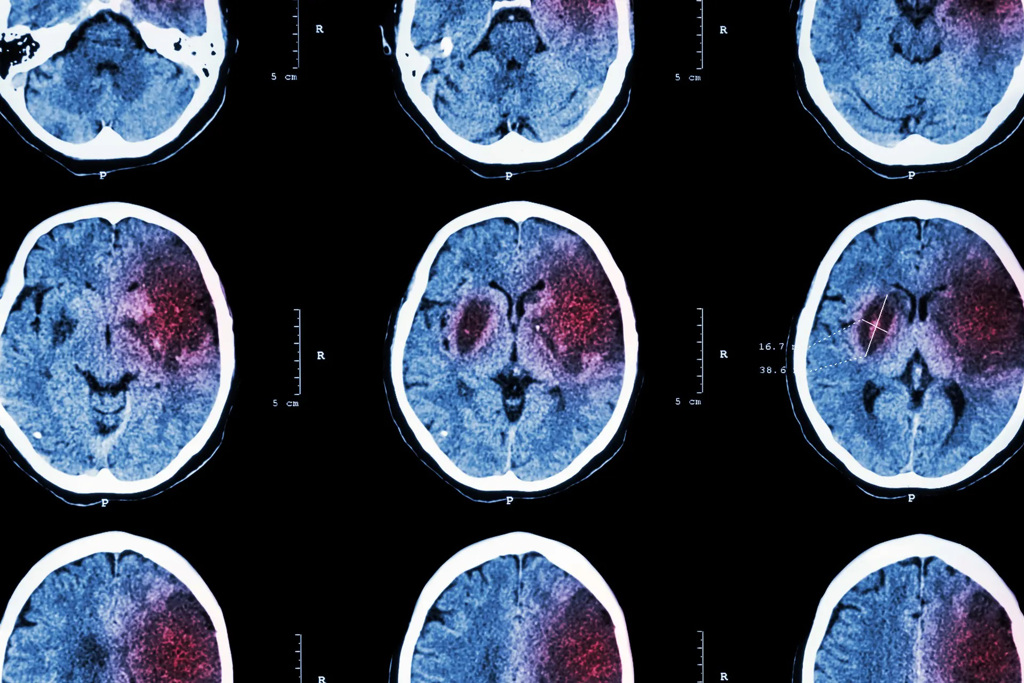

電腦斷層顯示,利用IGF-1荷爾蒙治療腸道,可以減小了因中風而缺乏血液、氧氣和營養的區域。(圖/德州農工大學)

研究人員發現,IGF-1確實有治療的效果,並且取決於其給藥途徑。以靜脈注射IGF-1,使其在血流中流動,可以減少血管梗塞面積,並在短期內改善感覺運動性能,從而產生「強大的神經保護」 。- 新聞來源於其它媒體,內容不代表本站立場!